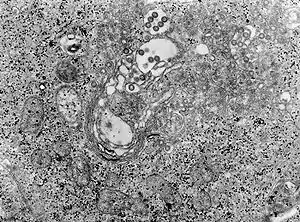

| Tissue infected with the Rift Valley fever virus | |